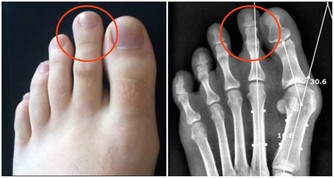

是由於變老的生理變化和病理變化,使患病的機率升高,衰老本身就是許多疾病的風險因素。

所以,變老不僅包括機體生理上的衰退,也包括在這個過程中發生的病理變化。

但是機體的這些病理變化,在沒有達到一定量的時候可以不發病;

只有病理變化累積達到一定程度,機體自身無法修復或及時修復的時候,才會出現生病的症狀。